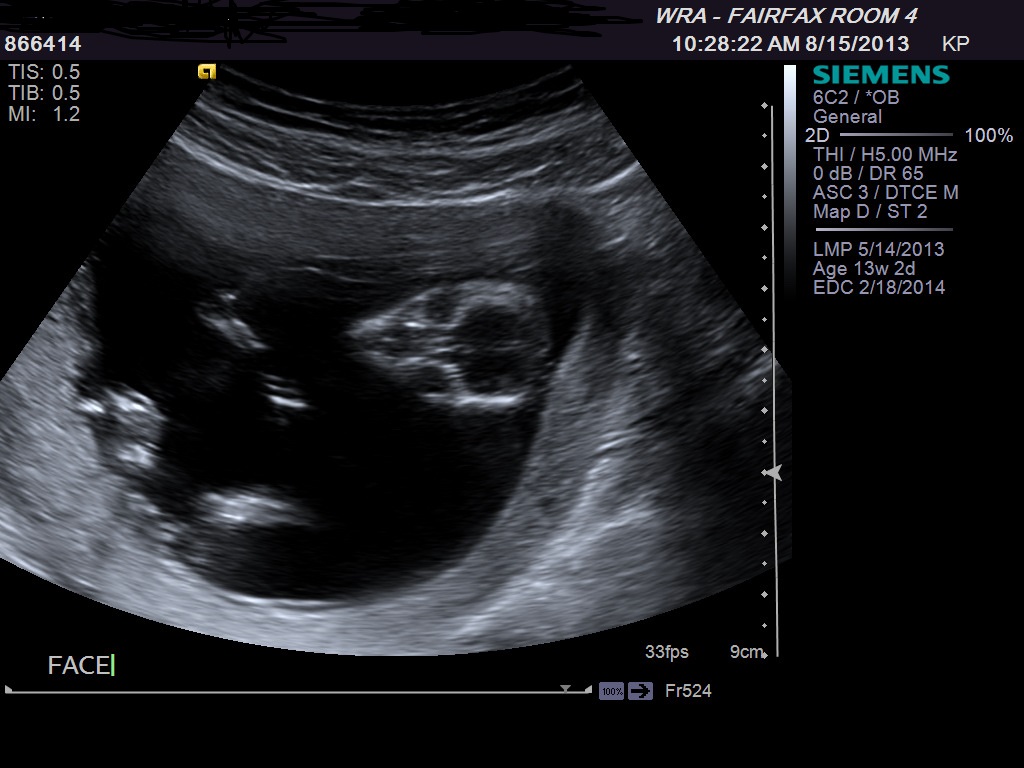

ultrasound 13 weeks is it boy or girl

Attachment 13977

When nub is easy to find